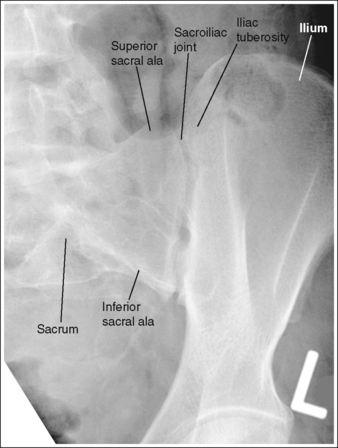

See Figure 7-32 and Box 7-7.

The sacroiliac joints are demonstrated in an AP axial projection. The median sacral crest is aligned with the symphysis pubis and the sacrum is at an equal distance from the lateral wall of the pelvic brim on both sides.

See Figure 7-34 and Box 7-8.